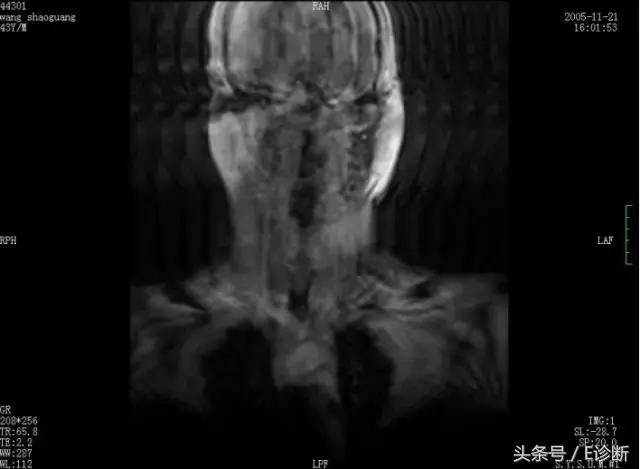

截断伪影

原因: 有限的采样次数和采样时间不能准确描述一个阶梯状信号的强度变化。

伪影特点: 相位方向更常见,在高对比度界面(颅骨/脑、脊髓/CSF、半月板/液体等)形成交替的亮带和暗带。

解决办法:

增加采样时间(减小带宽)以减小波纹

降低像素大小(增加Np或减小FOV)